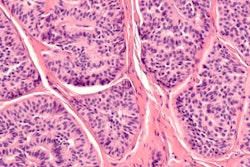

This study enrolled 30 patients (18 males and 12 females) with histologically confirmed neuroendocrine tumors and who were scheduled for routine PET/CT scans (Biograph mCT 128, Siemens Healthcare) with Ga-DOTATOC.